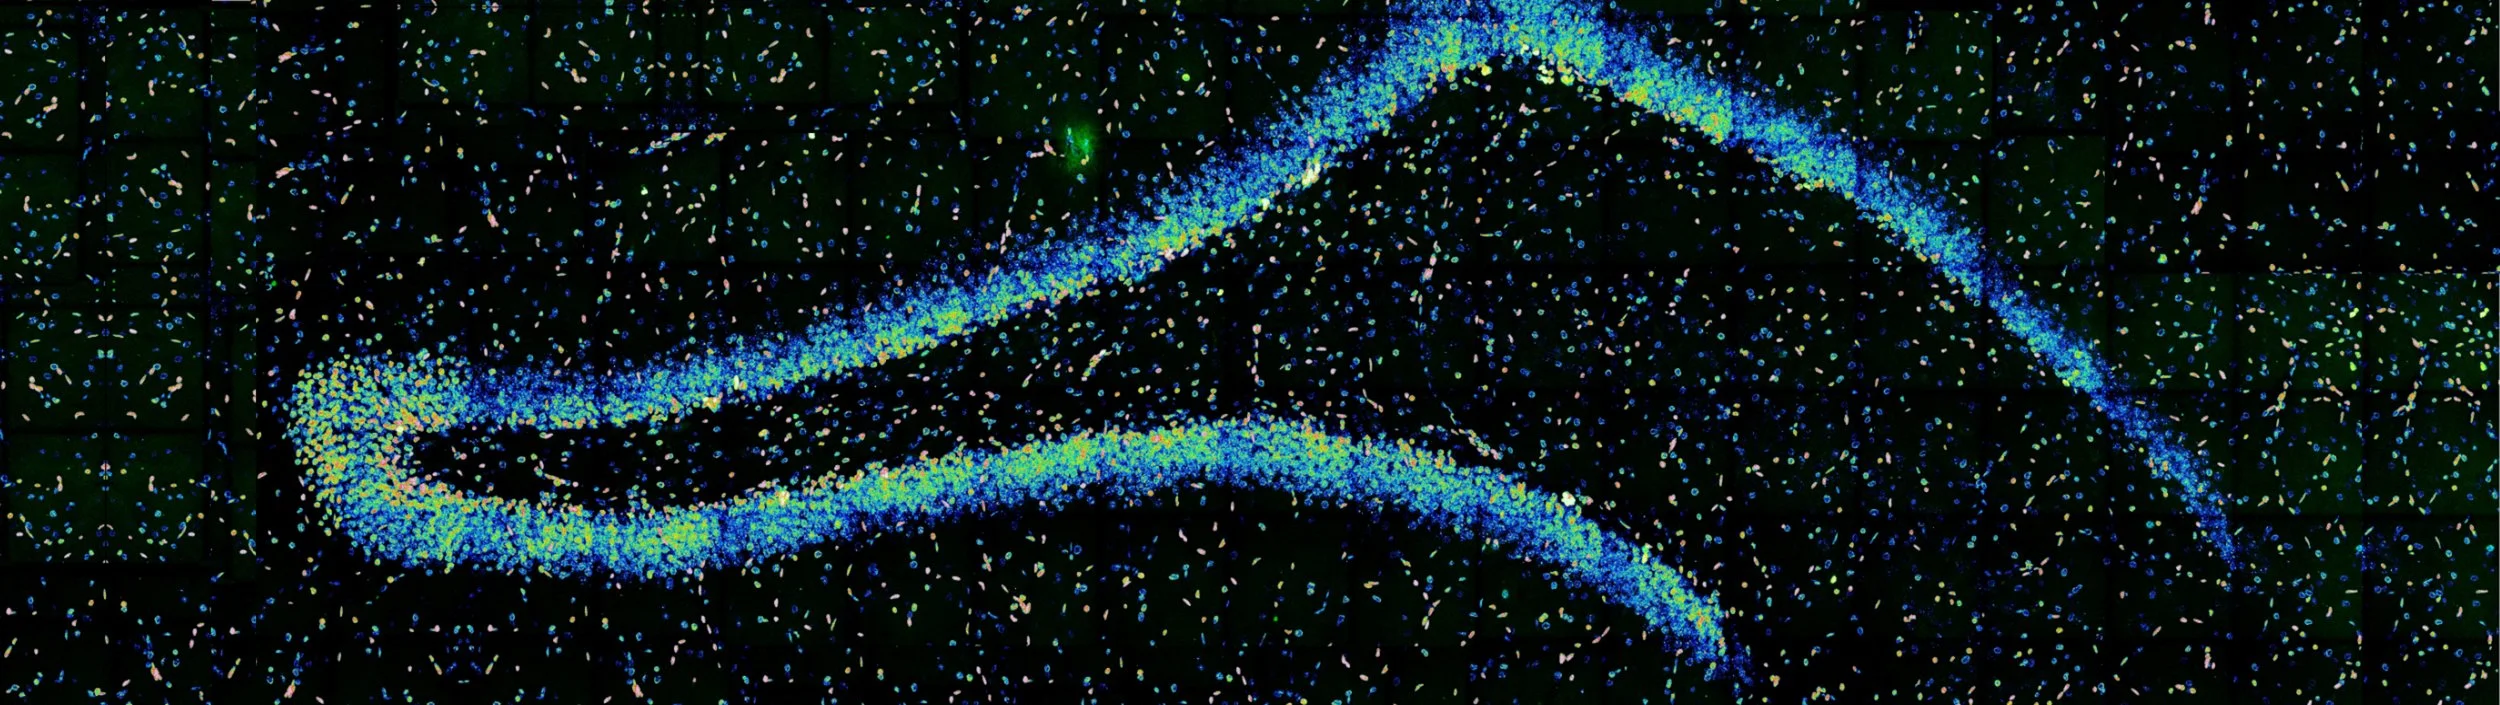

Brain-derived neurotrophic factor (BDNF) is a key neurotrophin that supports neuronal survival, differentiation, and synaptic plasticity. It plays a central role in learning, memory, and overall brain function. Alterations in BDNF signaling have been consistently observed across a wide range of diseases, including neurodegenerative disorders, psychiatric illnesses, and neurodevelopmental diseases. Disruptions in its pathways are considered fundamental contributors to disease mechanisms of these pathological conditions. BDNF is also a critical molecule within the heart–brain axis, and maintaining its balance is essential for both neural and cardiovascular health.

1: Investigate the molecular mechanisms underlying the dysfunction of neurotrophic factors, particularly BDNF, in different pathological conditions, including Alzheimer’s disease, epilepsy, and Rett syndrome.

Epilepsy

Epilepsy affects over 100,000 people in Portugal and between 50 and 65 million people worldwide. This brain disorder is characterized by an enduring predisposition to generate epileptic seizures and impacts patients on multiple levels (biological, psychological, and social). Currently, antiseizure drugs (ASDs) only control the symptoms (seizures), highlighting the urgent need to develop disease-modifying therapies.